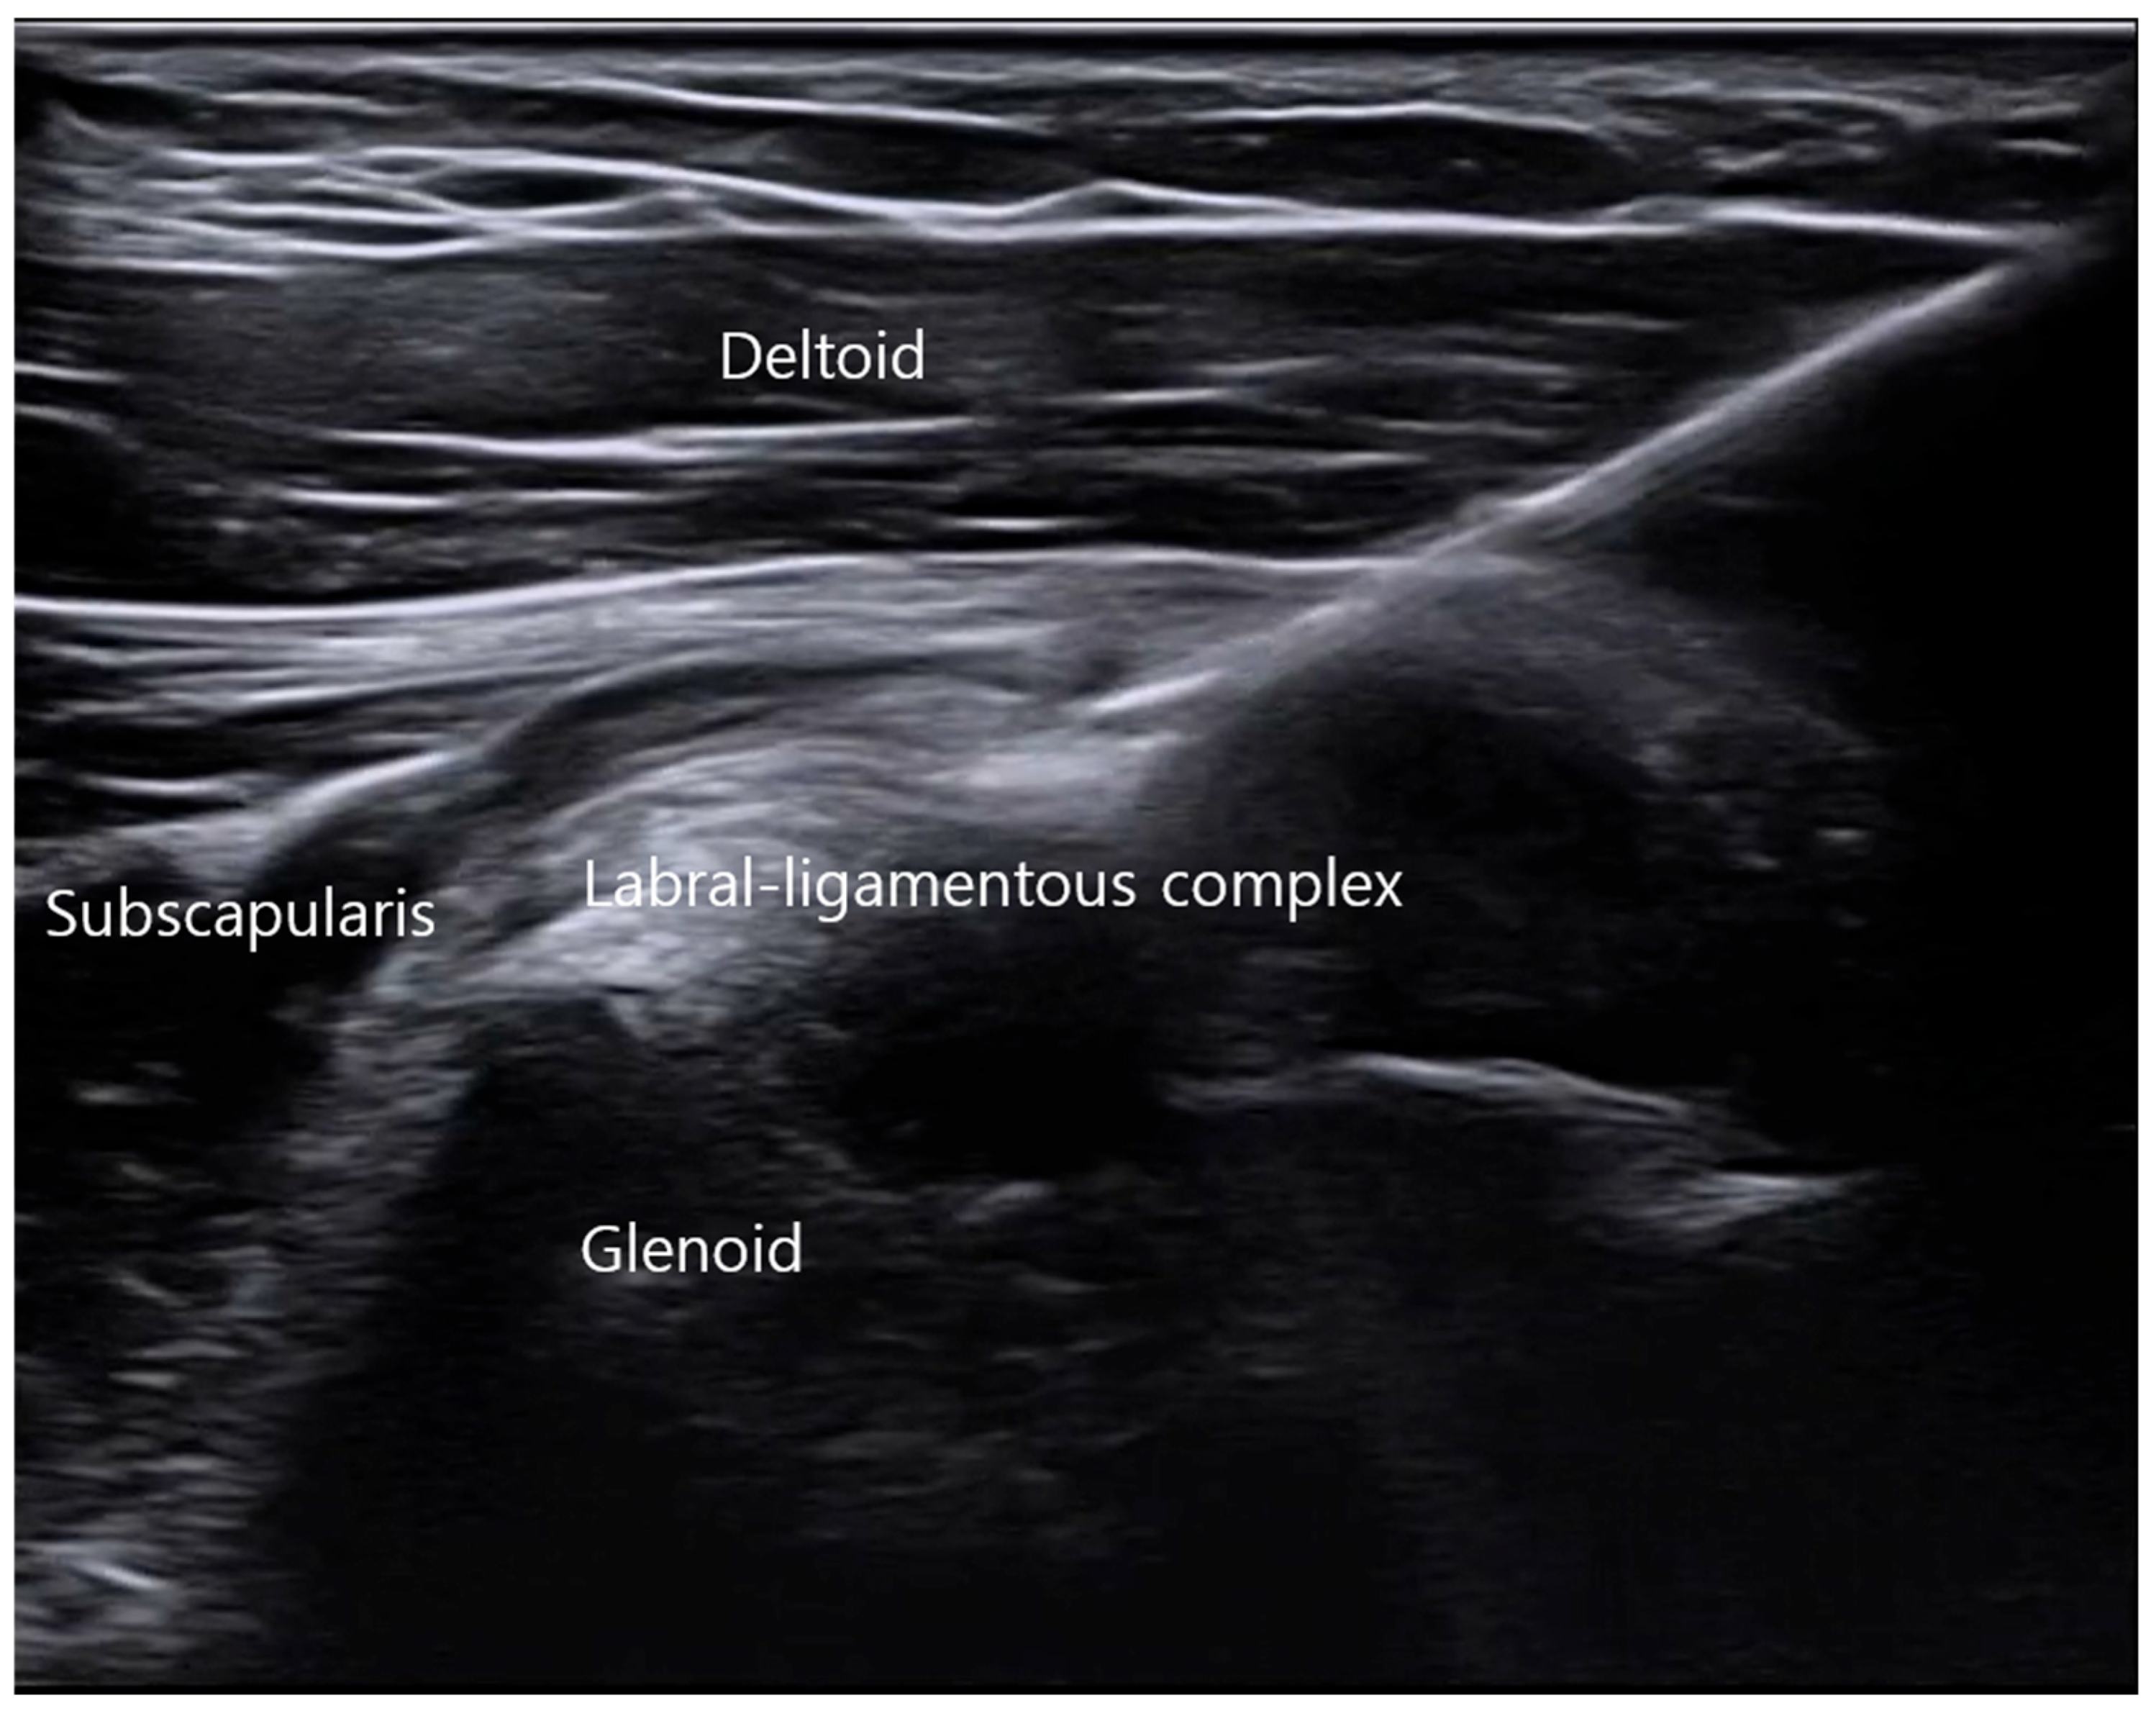

3.1. Ultrasound Landmark Identification and Localization of the ALLC

3.2. Ultrasound-Guided In-Plane Injection